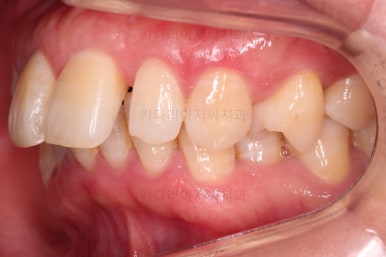

초진 시, 입안의 모습이에요.

"최근 들어 점점 틀어지고, 점점 튀어나오고, 점점 사이가 벌어져요."

성장이 끝난 성인들은 해가 갈수록 특히 아래앞니가 삐뚤어지는 것은 자연스러운데요.

이번 환자분의 말씀대로 최근에 변하가 심하게 나타난 경우는 원인이 딱 하나에요.

잇몸(치주)

흔히 풍치라고 하죠.

전반적인 잇몸이 나빠진다 -> 어금니가 씹는 힘에 버텨주지 못하고 앞으로 쓰러진다. -> 앞니가 강하게 부딪히며 아래앞니가 윗니를 앞으로 쳐낸다. -> 돌출입이 생기고, 앞니 사이 틈새가 생긴다.

앞니가 튀어나오고 틈새가 생기는 것이 결과이긴 하지만 원인은 어금니쪽 잇몸에서부터 찾아야해요.